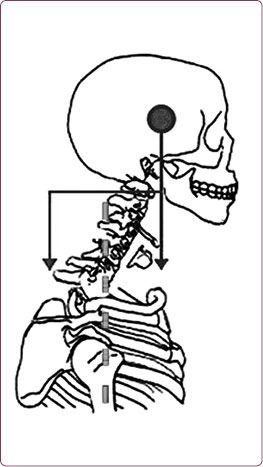

В этом случае центр тяжести головы вынесен вперед относительно центра тяжести тела (рис. 10, 11).

Рис. 10. «Компьютерная» постановка шеи

Рис. 11. Распределение силы тяжести при «компьютерной» шее

При эталонной осанке нагрузка на позвоночник составляет 4–5 кг. Если голова выдвинута вперед всего на 2,5 см, нагрузка на шейный и грудной отделы позвоночника вырастает на 5 кг.

Как будто бы вы носите мешок с картошкой на шее и пытаетесь ему сопротивляться, вытягивая шею вверх, чтобы смотреть вперед.

Этот мешок давит на седьмой шейный позвонок, трапециевидные мышцы, лопатки, ключицы и загрудинное пространство, стягивая вниз платизму (поверхностную мышцу шеи).

Несовпадение центра тяжести головы с гравитационной вертикалью тела неизбежно повлечет за собой изменение всей осанки. В первую очередь – сутулость – избыточный грудной кифоз.